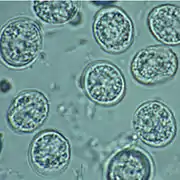

Tachyzoites

Motile, and quickly multiplying, tachyzoites are responsible for expanding the population of the parasite in the host.[45][28]: 19 When a host consumes a tissue cyst (containing bradyzoites) or an oocyst (containing sporozoites), the bradyzoites or sporozoites stage-convert into tachyzoites upon infecting the intestinal epithelium of the host.[28]: 359 During the initial acute period of infection, tachyzoites spread throughout the body via the blood stream.[28]: 39–40 During the later, latent (chronic) stages of infection, tachyzoites stage-convert to bradyzoites to form tissue cysts.

Intermediate hosts found include pigs, chickens, goats, sheep[28]: 2 and Macropus rufus by Moré et al. 2010.[33]: 162 Cattle and horses are resistant and thought to be incapable of significant infection.[28]: 11 T. gondii is considered to have three stages of infection; the tachyzoite stage of rapid division, the bradyzoite stage of slow division within tissue cysts, and the oocyst environmental stage.[34] Tachyzoites are also known as "tachyzoic merozoites" and bradyzoites as "bradyzoic merozoites".[35] When an oocyst or tissue cyst is ingested by a human or other warm-blooded animal, the resilient cyst wall is dissolved by proteolytic enzymes in the stomach and small intestine, freeing sporozoites from within the oocyst.[30][34] The parasites first invade cells in and surrounding the intestinal epithelium, and inside these cells, the parasites differentiate into tachyzoites, the motile and quickly multiplying cellular stage of T. gondii.[28]: 39 Tissue cysts in tissues such as brain and muscle tissue, form about 7–10 days after initial infection.[34] Although severe infection of M. rufus has been observed it is unknown whether this is common.[33]

Inside host cells, the tachyzoites replicate inside specialized vacuoles (called the parasitophorous vacuoles) created from host cell membrane during invasion into the cell.[28]: 23–39 Tachyzoites multiply inside this vacuole until the host cell dies and ruptures, releasing and spreading the tachyzoites via the bloodstream to all organs and tissues of the body, including the brain.[28]: 39–40